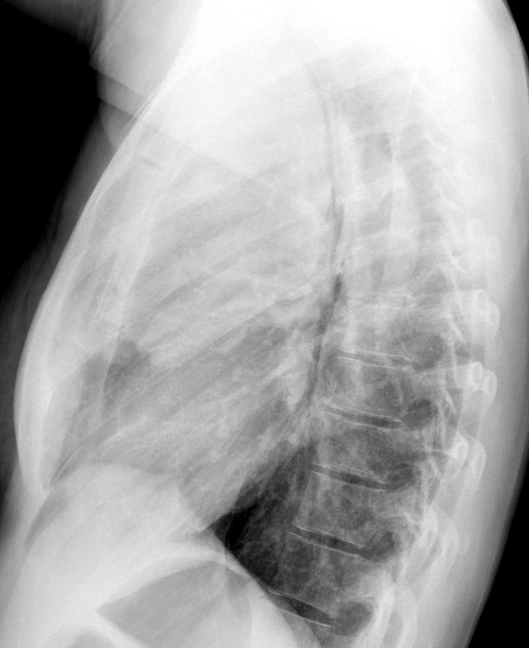

Gallery Mediastinum Lymphoma 7b

7b